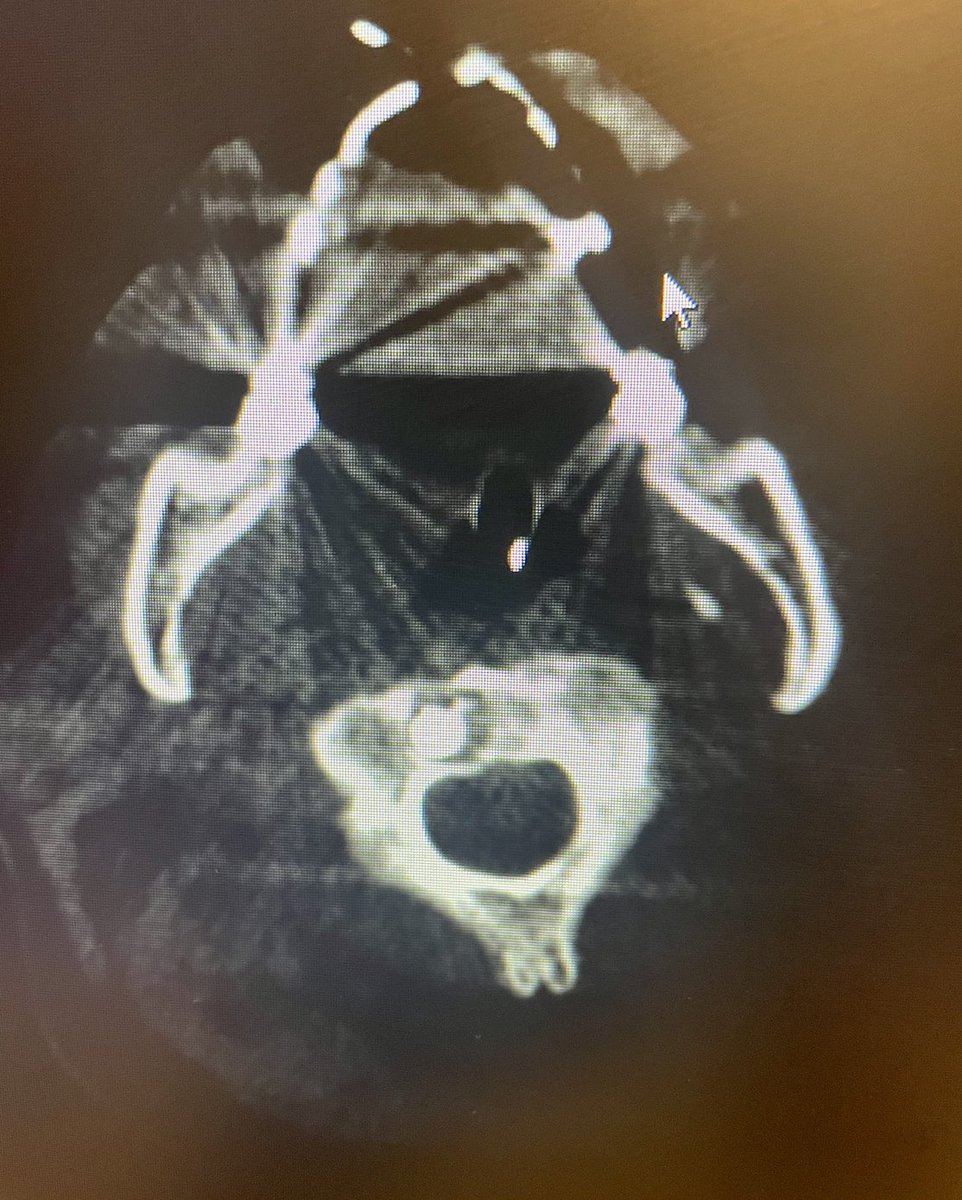

.@LucasRCmd, MPH; @HiroSparks, MD; Kara E. Masterson, MSN, NP; Scott J. Genshaft, MD; @AdamPlotnik, MD; and Siddharth A. Padia, MD, contributed to this open access article. See what they've been working on! brnw.ch/21wPx6v